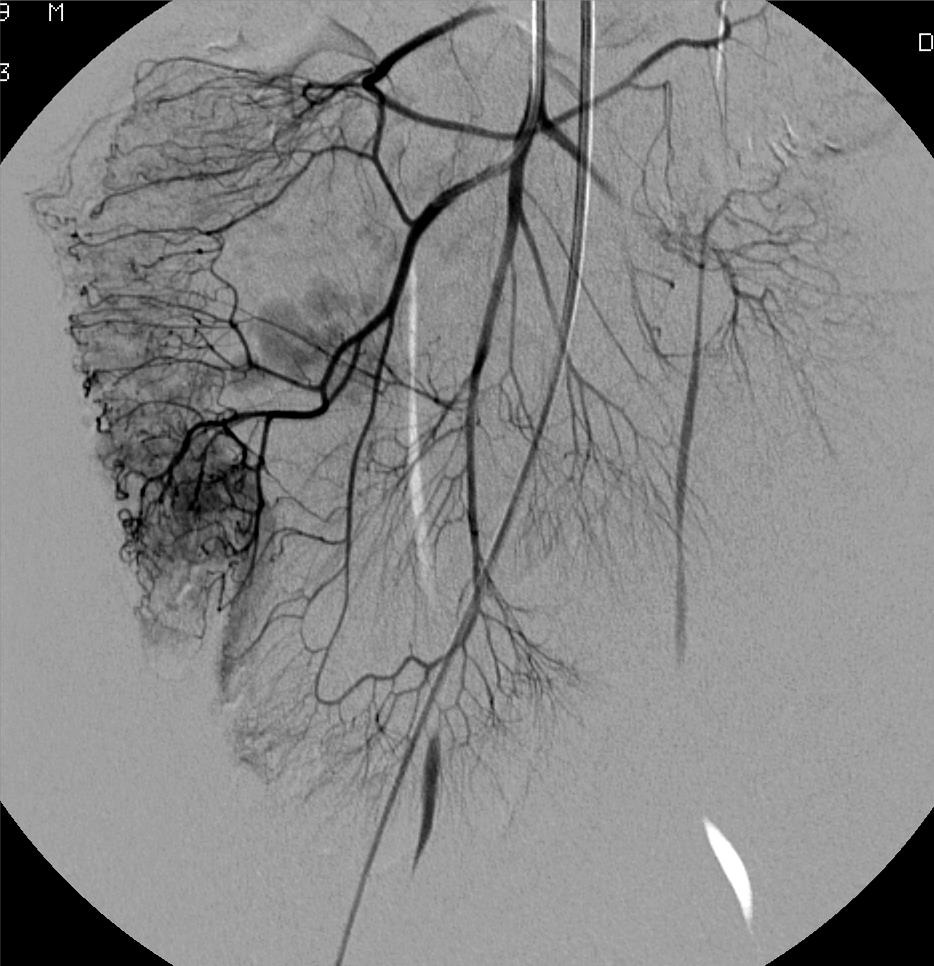

下消化道出血栓塞技术:血管造影的处理

结肠 Colonic 通常是憩室 Usually diverticular 空肠和回肠 血管造影对于病因的诊断可能并不明显Underlying diagnosis may not be apparent on angiography 虽然栓塞可能成功地控制出血,但重要的是随后的检查以确定病因 Whilst embolization may successful

单来源出血 Single point source of bleeding

• 常见 Most common finding

多来源出血 Multiple point sources

• 少见 Less common

• 每个出血点尽可能分别栓塞 Each source should be embolized as selectively as possible

• 不要试图近端栓塞 Do not be tempted to embolize more proximally